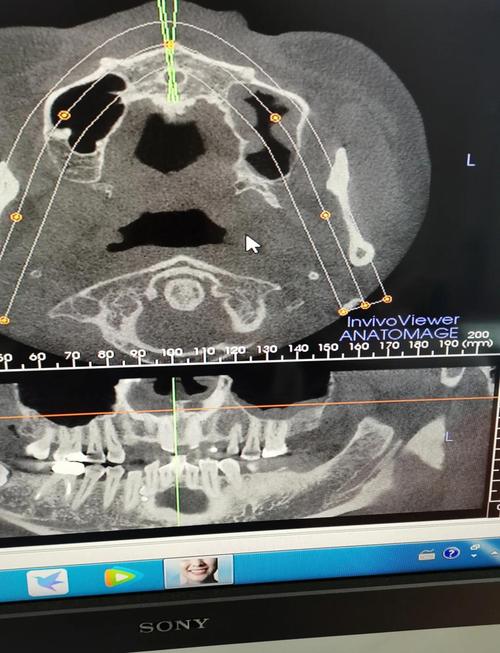

北医分析的技术内核首先体现在数字化数据采集与三维重建上,传统正畸诊断依赖X线头影测量(二维)和石膏模型(实体),存在数据维度单一、操作误差大等问题,北医体系则全面引入锥形束CT(CBCT)、口内扫描仪、面部三维摄影等设备,获取颅颌骨的立体影像、牙列形态及面部软组织轮廓,CBCT可重建颌骨的3D模型,精确测量牙根位置、骨皮质厚度、上颌窦与牙根的距离等关键参数,避免二维影像的放大误差和重叠干扰;口内扫描仪则能在5分钟内获取高精度的牙列数字模型,替代传统取模的不适感,且数据可直接用于3D打印导板或数字化方案设计,在此基础上,北医分析通过专业软件(如Dolphin Imaging、3Shape OrthoAnalyzer)进行多模态数据融合,将骨性结构、牙列位置、咬合关系、面部软组织特征整合到同一坐标系中,实现“从骨到牙、从牙到面”的全面评估。

在生物力学分析与方案优化环节,北医分析突破了传统经验式设计的局限,通过有限元分析(FEA)技术,可模拟牙齿在不同矫治力作用下的移动路径、牙槽骨改建应力分布及邻牙影响,针对骨性Ⅲ类错颌患者,北医团队会通过FEA模拟上颌骨前方牵引的力学效果,优化牵引力的方向、大小及作用时间,避免牙根吸收或骨开裂等风险;对于复杂牙列拥挤病例,则可通过虚拟排牙功能,在计算机中模拟牙齿移动的最终位置,提前判断是否需要拔牙、支抗设计等关键问题,北医分析还注重颅颌面生长发育的动态评估,对青少年患者结合手腕骨龄片、颈椎侧位片判断生长潜力,通过生长改型治疗(如功能性矫治器)引导颌骨正常发育,而非单纯依赖牙齿代偿。